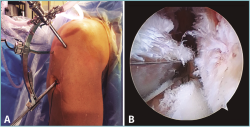

• Técnicas transtibiales: son las técnicas más utilizadas para la realización de la raíz posterior por su mayor facilidad de realización respecto a las técnicas in situ. Para su aplicación se realiza un túnel transóseo desde la cortical tibial anterior hasta la zona de inserción anatómica de la raíz en cuestión con la ayuda de una guía de LCA (Figura 8) desde una incisión accesoria anteromedial o anterolateral (en función del menisco afectado se utiliza una u otra, desde el lado contralateral para seguir la dirección de las fibras de inserción de la raíz intervenida); en caso de reconstrucción asociada de LCA, se puede utilizar la misma incisión anteromedial; algunos autores incluso proponen la utilización del mismo túnel para la reconstrucción del LCA y de la raíz meniscal(68). Los hilos con los que se realiza la sutura meniscal se introducen a través del túnel tibial para realizar la fijación dentro del túnel(68) y/o en la cara anterior de la tibia, mediante puente óseo (realizando doble túnel)(69), con un botón(11), con un implante sin hilos(12) o a un poste(70).

Figura 8. Colocación de la aguja-guía para la realización del túnel tibial en una reinserción transósea de la raíz posterior del menisco lateral. A: imagen exterior; B: imagen artroscópica. LFC: cóndilo femoral lateral; LTP: platillo tibial lateral. Reproducido con permiso de Espejo-Baena A, et al. Arthrosc Tech. 2017 May 22;6(3):e621-e626(12).